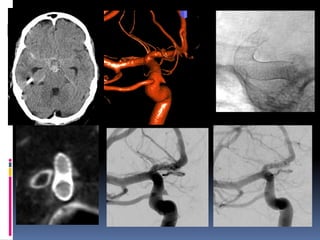

Classical blister aneurysm

34-year M, SAH